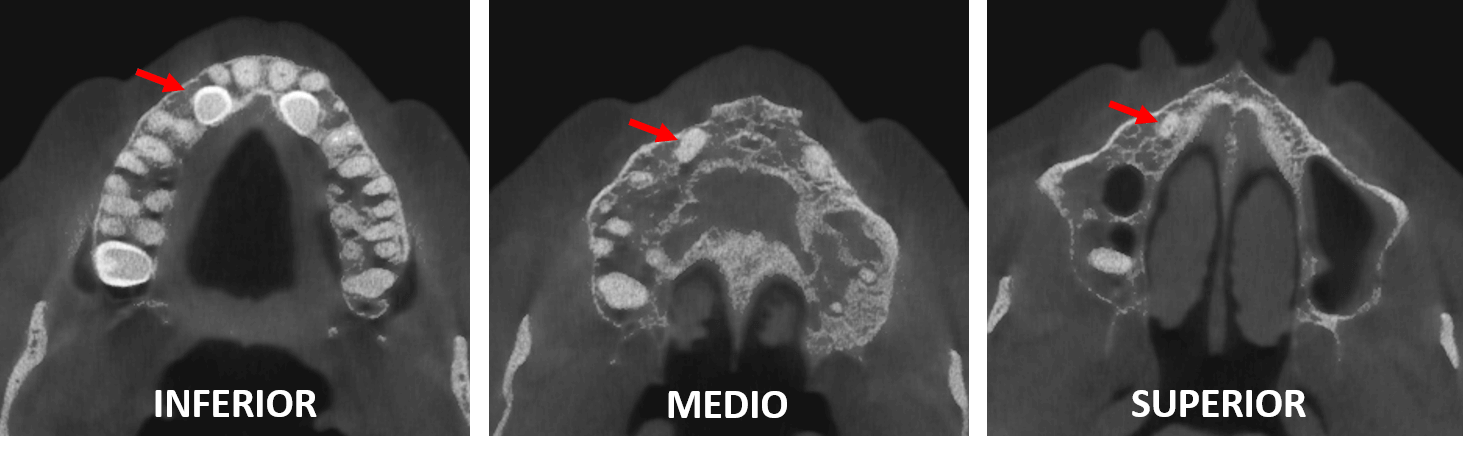

Fig.3

En cortes axiales (Fig.3) se observa disposición del órgano dentario 13 (flechas rojas) y su relación con las tablas ósea vestibular y palatina, asi como con el órgano dentario 12. Nótese que el órgano dentario 23 presentan una disposición similar al del órgano dentario 13.